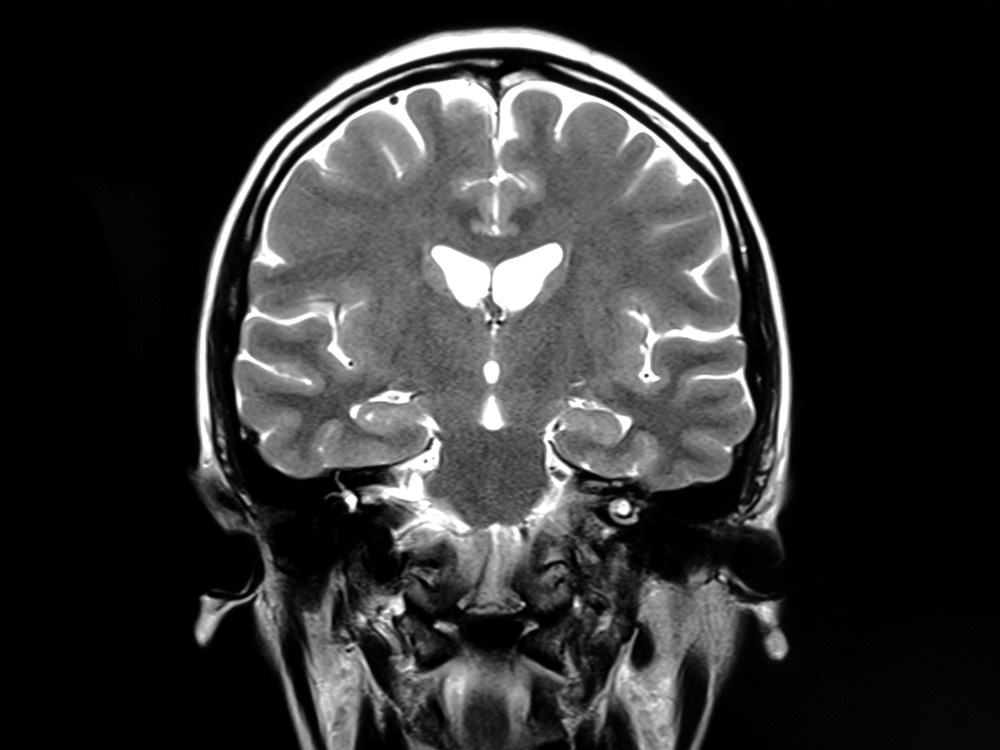

In the present study, researchers investigate changes in the thickness and volume of gray matter (GM) and white matter (WM) microstructural abnormalities. A total of 56 COVID-19 patients and 37 healthy controls were included in the current study to assess and compare their cognitive capabilities and fatigue levels using magnetic resonance imaging (MRI).

T1-weighted MRI scans were used to assess GM thickness and volume. Diffusion-weighted MRI (d-MRI) was used to extract fiber-specific apparent fiber density (FD), free water (FW) index, and diffusion tensor imaging (DTI) data to assess WM microstructural changes. Apparent fiber density (AFD) represents axonal degeneration, whereas DTI assesses WM integrity.

The MRI data were collectively used to estimate cortical thickness, the distance between the WM and GM boundaries and the pial surface, as well as deep GM nuclei volume. Cortical parcellation maps allowed for the detection of sub-millimeter differences between groups, wherein a circularly symmetric Gaussian kernel smoothened the maps.